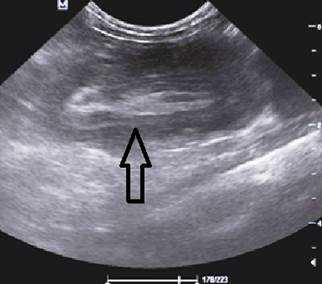

На рисунках 2 и 3 отображена ультразвуковая картина кишечной инвагинации.

Рис. 2. Симптом «мишени»

Комментарии: основным методом в дополнительной диагностике инвагинации кишечника является УЗИ органов брюшной полости. Этот метод обладает 100-процентной диагностической достоверностью и специфичностью в отношении инвагинации кишечника. УЗ-признаками инвагинации кишечника является обнаружение симптома «мишени» или «псевдопочки». Симптом «мишени» заключается в наличии на поперечном срезе двух колец низкой эхоплотности, разделенных гиперэхогенным кольцом. Симптом «псевдопочки» виден на продольном срезе и представляет собой наслаивающиеся друг на друга гипер- и гипоэхогенные слои.